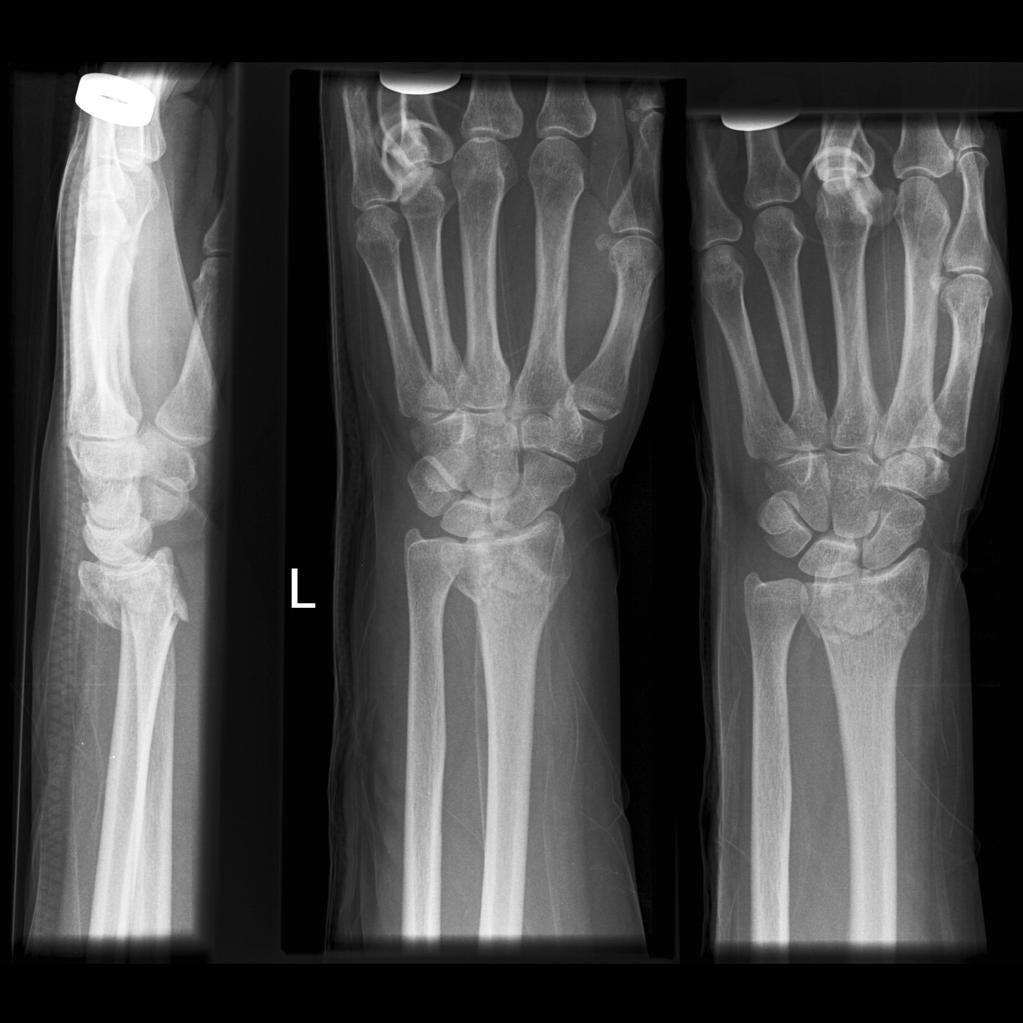

What is a Colles’ fracture?

An extra articular fracture of the distal radius within an inch of the articular surface and with dorsal displacement or angulation

A Colles’ fracture is commonly associated with fracture of what else?

Ulnar styloid process

What is a Smith’s fracture?

A volarly displaced or angulated extra-articular fracture of the distal radius

A _________ fracture involves a volarly displaced distal radius, whereas a _________ involves a dorsally displaced distal radius

A Smith’s fracture involves a volarly displaced distal radius, whereas a Colles’ involves a dorsally displaced distal radius